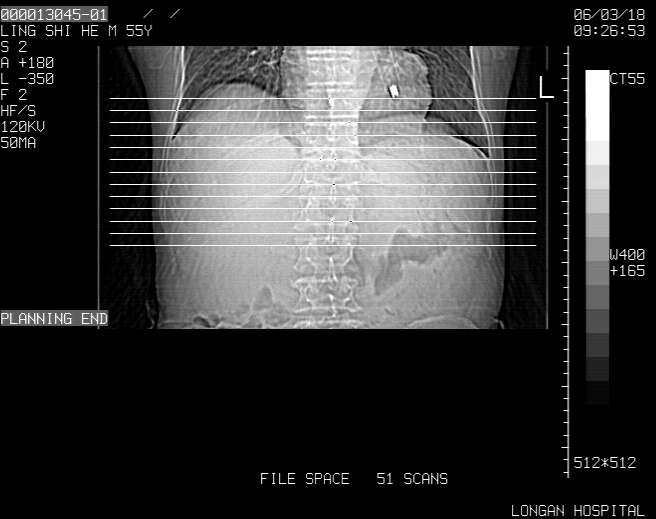

以下是引用guzhongliangddd在2006-3-21 22:13:00的发言:[br]病灶主要位于肝右叶的后份,内见异常血管,门脉主干及右支受侵{提示有癌栓形成},门腔间隙内见增大淋巴结。肝左叶内未见异常。

以下是引用zhuxinli在2006-3-22 1:23:00的发言:[br][br] 病灶主要位于肝右叶的后份,内见异常血管 .门脉右支截断,右叶前段早期强化(考虑动静脉漏),腹膜后肿大淋巴结,病灶逐渐强化,考虑为胆管细胞癌[br]